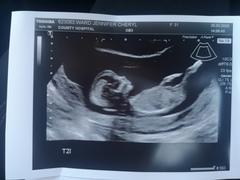

Had my scan yesterday putting me slightly more ahead at 13+3. Both babies lovely and wriggly, neither really wanting selfies as kept turning away. Twin 2 was very chilled out just hanging around with legs stretched and crossed and arms behind head lol. Starting to feel so more real again. Having another phase of oh shit, there's two humans inside of me! 🤯

@Sunflower1608 that's brilliant news and those are gorgeous clear scan pictures! Measuring ahead with twins is great. Pleased you've had a nice positive scan